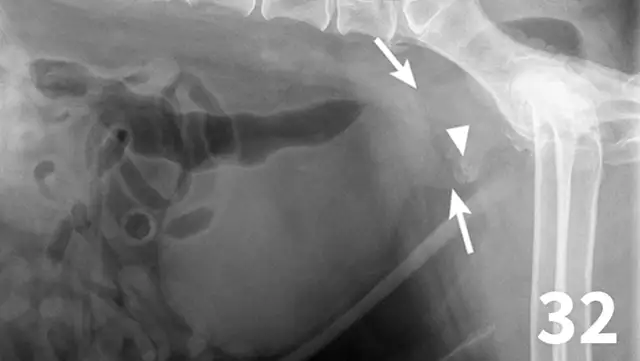

Survey abdominal radiographs (Figures 1 and 2) offer important information on kidney number, size, shape, symmetry, and location, as well as the presence of any mineralized opacities (eg, calcified tissue, nephroliths). The utility of abdominal radiographs is decreased in patients with abdominal fluid or lack of abdominal fat (eg, young or emaciated patients) because of lack of contrast. Excretory urography (IV pyelography), although more invasive, can augment survey radiographs and provide information about renal parenchymal architecture (eg, filling defects associated with cysts or infiltrative disease), the renal pelvis, and ureters as well as a qualitative assessment of global and individual renal excretory function (Figure 3).

Figure 1.

An enlarged left kidney with an irregular shape (arrows) is noted on the VD view of a dog with renal adenocarcinoma. The left kidney measured 4.5 times the length of L2; normal kidney length in the dog is 2.5 to 3.5 times the length of L2.